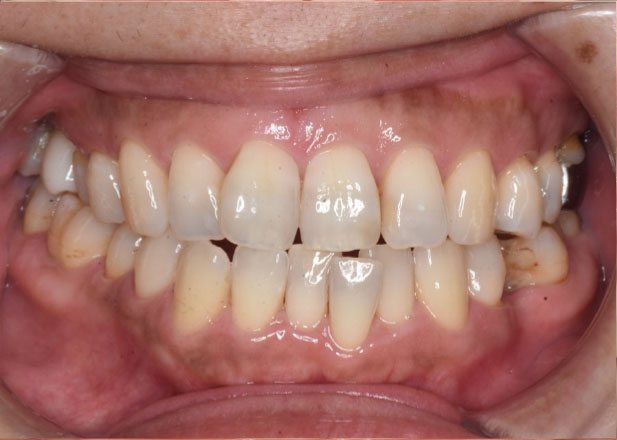

以前右上6にインプラント治療を行い、それを生かしながら、前歯の矯正を行いたいという患者様に治療を行いました。

インプラント治療を行った歯は動かすことができないので治療方針を立てる際に難易度が高まりますが、適切に診断することで安全に治療を行うことができます。右側下顎臼歯をカリエールシステムを用いて遠心移動させて、下顎前突傾向、非対称に対して治療を行いました。

治療後

マウスピース矯正 マウスピース矯正 マウスピース矯正